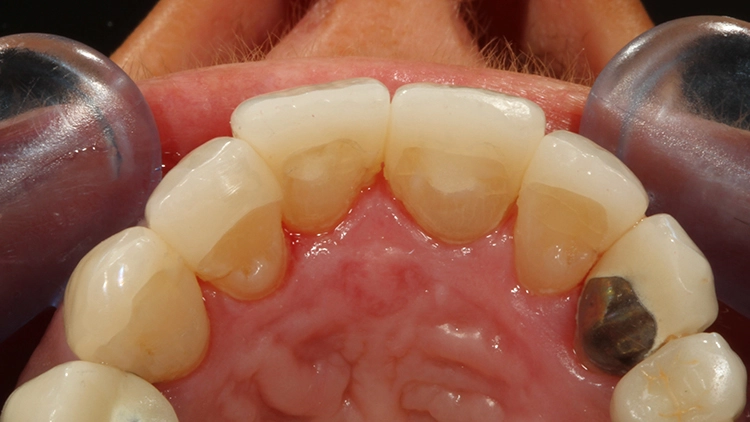

Bis zur definitiven prothetischen Versorgung sollte aufgrund etwaiger Gewebeveränderungen 6 Monate gewartet werden. Nach dieser Wartezeit zeigte sich ein stabiles, rezidivfreies parodontalchirurgisches Behandlungsergebnis (Abb. 8 und 9).

Bei der jetzt anstehenden Teilkronen- bzw. Veneerversorgung der Zähne 12 bis 23 blieb zunächst die Frage des keramischen Restaurationsmaterials zu klären. Neben der bewährten und hochästhetischen glasbasierten Keramik [2,8,10,14–16] eignen sich heutzutage transluzente Zirkonoxidmaterialien hervorragend für die ästhetische Ausgestaltung von Frontzahnbereichen [11], da sie genauso gut verklebt werden können wie Glaskeramiken [9,23].

Gerade im Bereich parafunktional gefährdeter Areale punktet das gegenüber der klassischen Glaskeramik doch deutlich bruchfestere Vollzirkonmaterial. Da bei der Patientin bereits mehrfach Füllungen und Inzisalkanten frakturierten, fiel in diesem Fall die Materialauswahl auf ein hochtransluzentes, polychromes Vollzirkon (zolid fx multilayer, Amann Girrbach), welches mit Ceramotion ZR (Dentaurum) verblendet wurde. Hergestellt wurde die Arbeit (Abb. 10 und 11) im eigenen Meisterlabor durch ZTM Richard Bohrer.